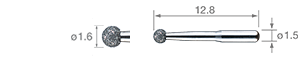

• Diamant beschichtete kugelförmige Spitze. Blutungen treten seltener auf.

• Diamant-Beschichtung

• Für NSK

• Diamant beschichtete kugelförmige Spitze. Blutungen treten seltener auf.

• Diamant-Beschichtung

• Bei molarer und interdentaler proximaler Karies. Mit der halbkugelförmigen Spitze wird das Schneiden in den gesunden Zahn vermieden.

• Diamant-Beschichtung

• Für NSK

• Für anteriore proximale Karies. Nur kariöses Dentin kann entfernt werden, z. B. bei Molaren.

• Diamant-Beschichtung

• Für NSK

• Bei molarer und interdentaler proximaler Karies. Mit der halbkugelförmigen Spitze wird das Schneiden in den gesunden Zahn vermieden.

• Diamant-Beschichtung

• Für NSK

• Für anteriore proximale Karies. Nur kariöses Dentin kann entfernt werden, z. B. bei Molaren.

• Diamant-Beschichtung